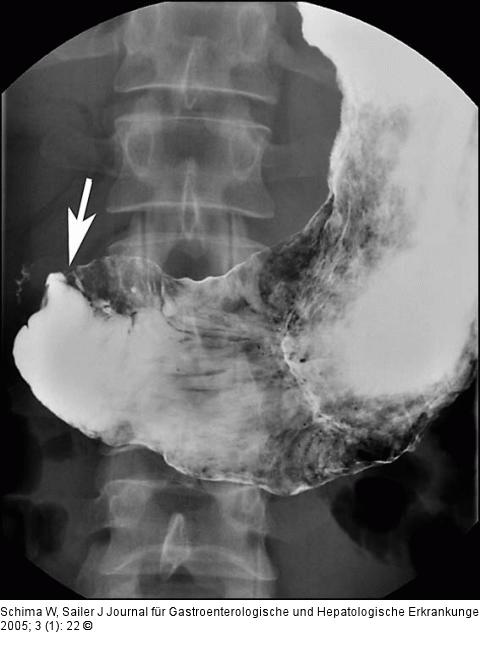

Abbildung 1: Morbus Crohn - Duodenum